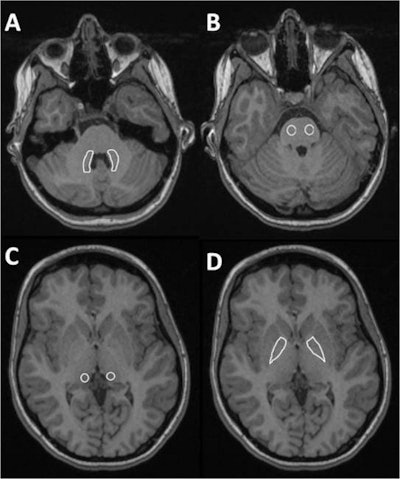

Rademacher undertook the survey of MRI contrast agent deposits in children as part of her doctoral thesis and was awarded the German Pediatric Radiology Association's 2016 science prize. Her group in Düsseldorf looked at over 8,000 head MRIs, and identified 24 children who had received at least nine examinations using macrocyclic GBCAs (gadoteridol and gadoterate meglumine). The group found no evidence the contrast medium accumulates in the nervous system.

To rule out age-related brain alterations, each child was assigned a comparator of the same age with no significant findings from a noncontrast head MRI. The signal intensities were then compared.

"We found the intensity was no higher than the control group in two relevant regions of the brain: the globus pallidus and dentate nucleus. And there was no correlation between number of MRIs and signal intensity," Klee noted in a statement released by the organizers of the RöKo.

The researchers interpreted this as evidence that macrocyclic GBCAs did not show significant accumulation in children's nerve tissue, and were safe even when administered repeatedly.